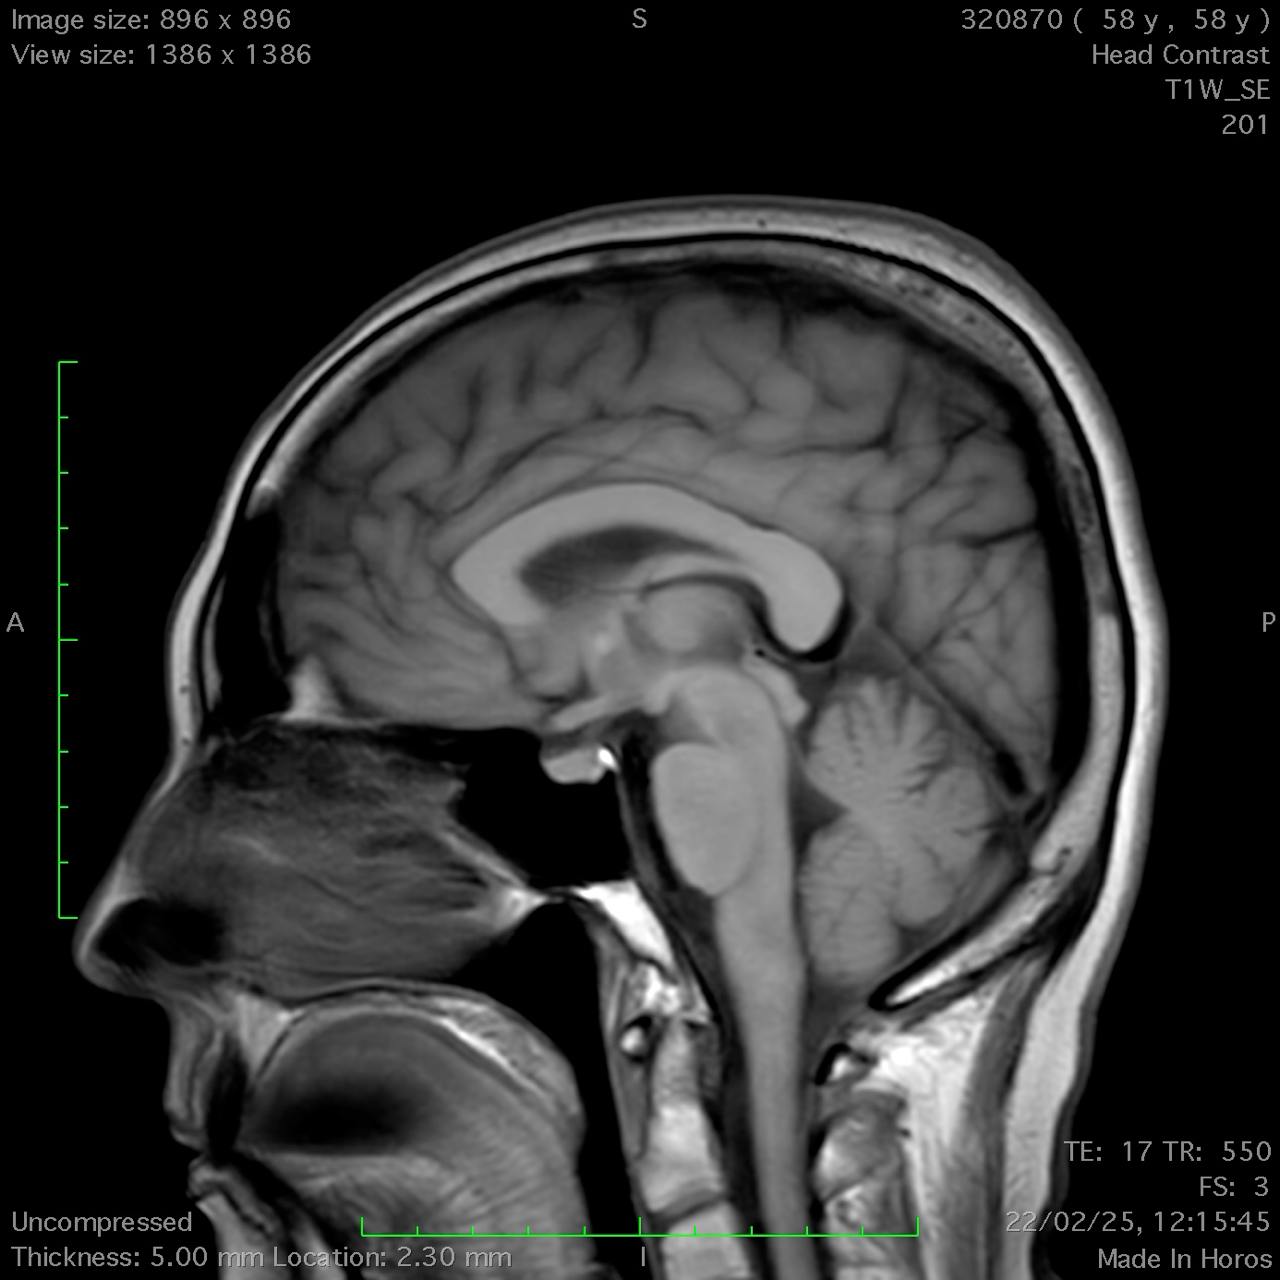

Results: Cerebellar ataxia, bilateral lower limb sensory loss, absent deep tendon reflexes, and marked bidirectional nystagmus were all found during the neurological test. Bilateral vestibular areflexia was established by video head impulse testing (vHIT). Electroneurography demonstrated sensory neuronopathy, and brain MRI showed mild cerebellar atrophy, particularly in the vermis, without evidence of central demyelination or structural abnormalities suggestive of other neurodegenerative conditions. The diagnosis of CANVAS was highly supported by the combination of clinical, electrophysiological, and imaging evidence, even if genetic confirmation was not feasible due to financial constraints CANVAS.

Conclusion: Suspicion of CANVAS should be raised in the presence of bilateral vestibular impairment, sensory neuropathy, progressive ataxia, and severe bidirectional nystagmus. The diagnosis is further supported by moderate cerebellar atrophy seen on MRI. When genetic testing is not available, a diagnosis can nevertheless be made using clinical and paraclinical findings, even though genetic testing is the gold standard for confirmation. Patient care can be enhanced, and needless treatments can be avoided, by recognizing CANVAS.

Sagittal T1-weighted MRI.